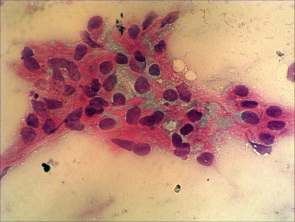

Cytological picture. There was no colloid in the background. Hyperchromatic epithelial columnar cells were found with clear cytoplasm. They were in irregular cell groups with loss of polarity and nuclear crowding.

Cytological diagnosis: a pattern corresponding to metastasis of the urinary bladder cancer.